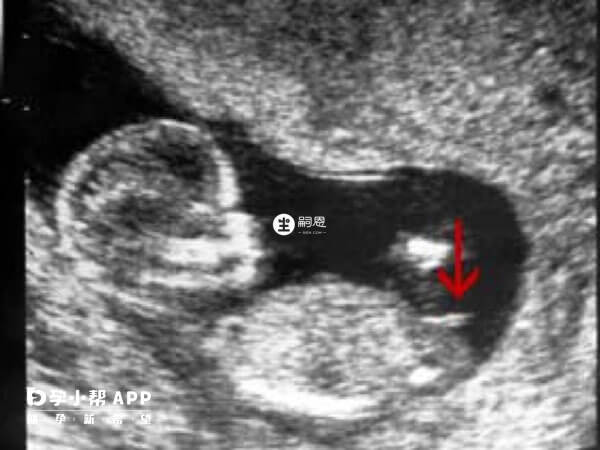

nt值看男孩女孩一般是通過生殖器部位和脊柱下部角度、胎兒姿勢以及nt資料等來判斷胎兒性別,nt圖和nt單資料是通過醫學檢查方法得出的結果,這也是這種方法比較流行的原因。但是這種方法並不準確,nt檢查是通過檢查胎兒頸項透明帶的厚度,可以在早期診斷出胎兒是否有脊柱裂、腦積水等先天性疾病,所以這種方法不能做為判斷胎兒性別的依據。從nt單子看男女是國外比較流行的判斷胎兒性別的方法,nt值看男孩女孩訣竅也有很多,一般是通過生殖器部位和脊柱下部角度、胎兒姿勢以及nt資料等來判斷胎兒性別,nt圖和nt單資料是通過醫學檢查方法得出的結果,這也是這種方法比較流行的原因。其實這種方法並不準確,nt檢查是通過檢查胎兒頸項透明帶的厚度,可以在早期診斷出胎兒是否有脊柱裂、腦積水等先天性疾病,這種方法不能做為判斷胎兒性別的依據。

nt檢查不能判斷胎兒性別,只是滿足了孕媽們對寶寶的好奇心,雖然不提倡孕媽們依賴這種手段去判斷寶寶性別,但好奇寶寶性別的孕媽不妨可以用這種方法來試一試,接下來詳細的介紹一下通過nt單子看男女的幾種方法,具體如下: